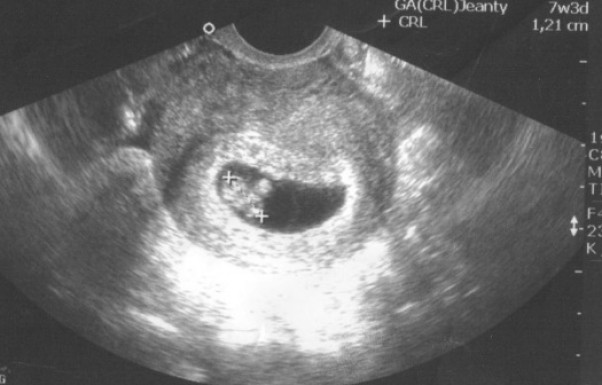

W końcu mam potwierdzenie na to że jest pod moim serduszkiem :) Pierwsza wizyta za nami i wiem że jest ok. Muszę brać witaminy dla kobiet w ciąży troszkę się oszczędzać i będzie dobrze :) i muszę zabrać milion kopii tego zdjęcia mężowi bo biega i wszystkim pokazuje że będzie miał dziecko-mój kochany wariat